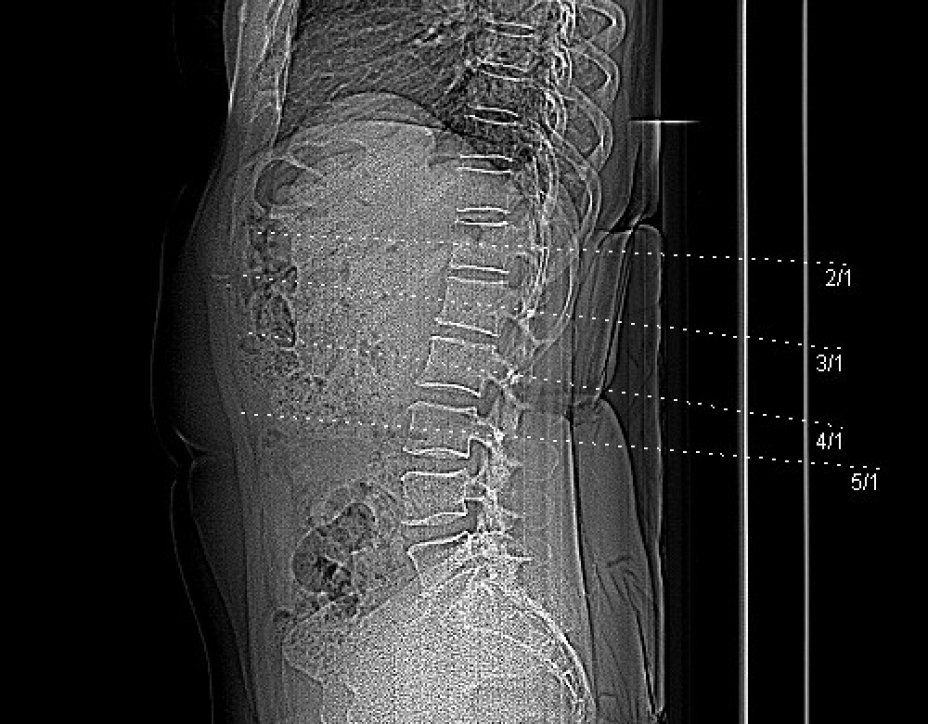

Die Knochendichtemessung mittels Computertomographie (Q.CT) ist eine der genausten Methoden zur Bestimmung der Knochendichte und gilt als Goldstandard. Sie ist sowohl für die Diagnosestellung als auch zur Verlaufskontrolle geeignet. Zur Bestimmung der BMD (engl.: Bone Mineral Density) werden bei der quantitativen Computertomographie ca. 3 bis 4 Scans von der Lendenwirbelsäule angefertigt. Aus der Knochendichte dieser Wirbelkörper wird der Mittelwert ermittelt. Dieser wird dann mit der Knochendichte eines gleichaltrigen Knochengesunden verglichen und in Relation dazu gesetzt. Je nach der Dichte des Knochens wird die Osteoporose dann in mehrere Stadien eingeteilt. Da die Knochendichtemessung (Q.CT) keine Kassenleistung ist, bieten wir die Untersuchung als

IGEL - Leistung an.

Q-CT gestützte Knochendichtemessung